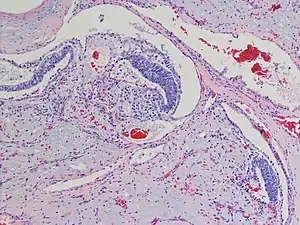

| Polyembryoma of the ovary, H&E stain | |

Polyembryoma is a rare, very aggressive form of germ cell tumor usually found in the ovaries. Polyembryoma has features of both yolk sac tumour and undifferentiated teratoma/embryonal carcinoma, with a characteristic finding of embryoid bodies lying in a loose mesenchymal stroma.